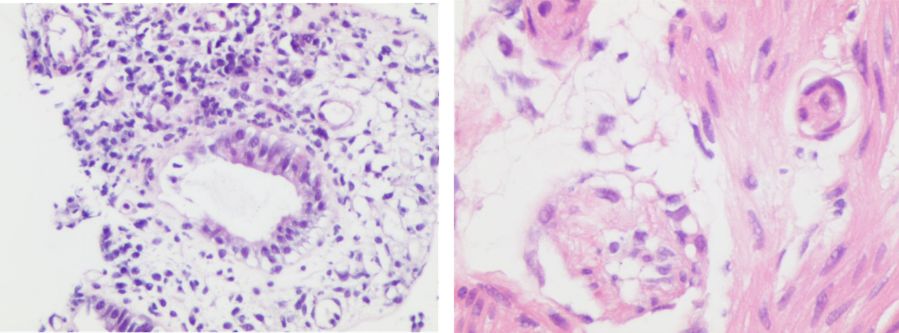

除了以上常见的三种活检类型外,内镜引导下的粘膜活检也是一类常见的活检类型,尤其常用于移植后怀疑移植物抗宿主病(GVHD)时。如图6左,通过粘膜活检我们看到腺体的上皮细胞发生了凋亡,腺体产生破坏且不完整,这就是GVHD的典型表现之一。此外我们还能看到毛细血管内的血栓生成,并且发生了激化(图6右)。

图6